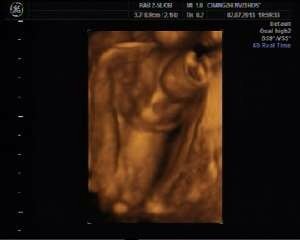

25周四维彩超看胎儿性别附照片 点击展开 匿名用户 2013-08-27 20:52 满意回答 恭喜发财,这是个男孩。 匿名用户 2013-08-28 10:38 宝宝知道提示您:回答为网友贡献,仅供参考。 相关问题 四维彩超看胎儿性别有没有出错的 25周胎儿四维彩超各项正常值是多少?做孕期糖尿病筛查,要做什么准备,什么时候做最好 怀孕25周了,还需要吃复合维生素(21)吗?做了个四维彩超,一切正常,还需要做其它什么检查呢?求回